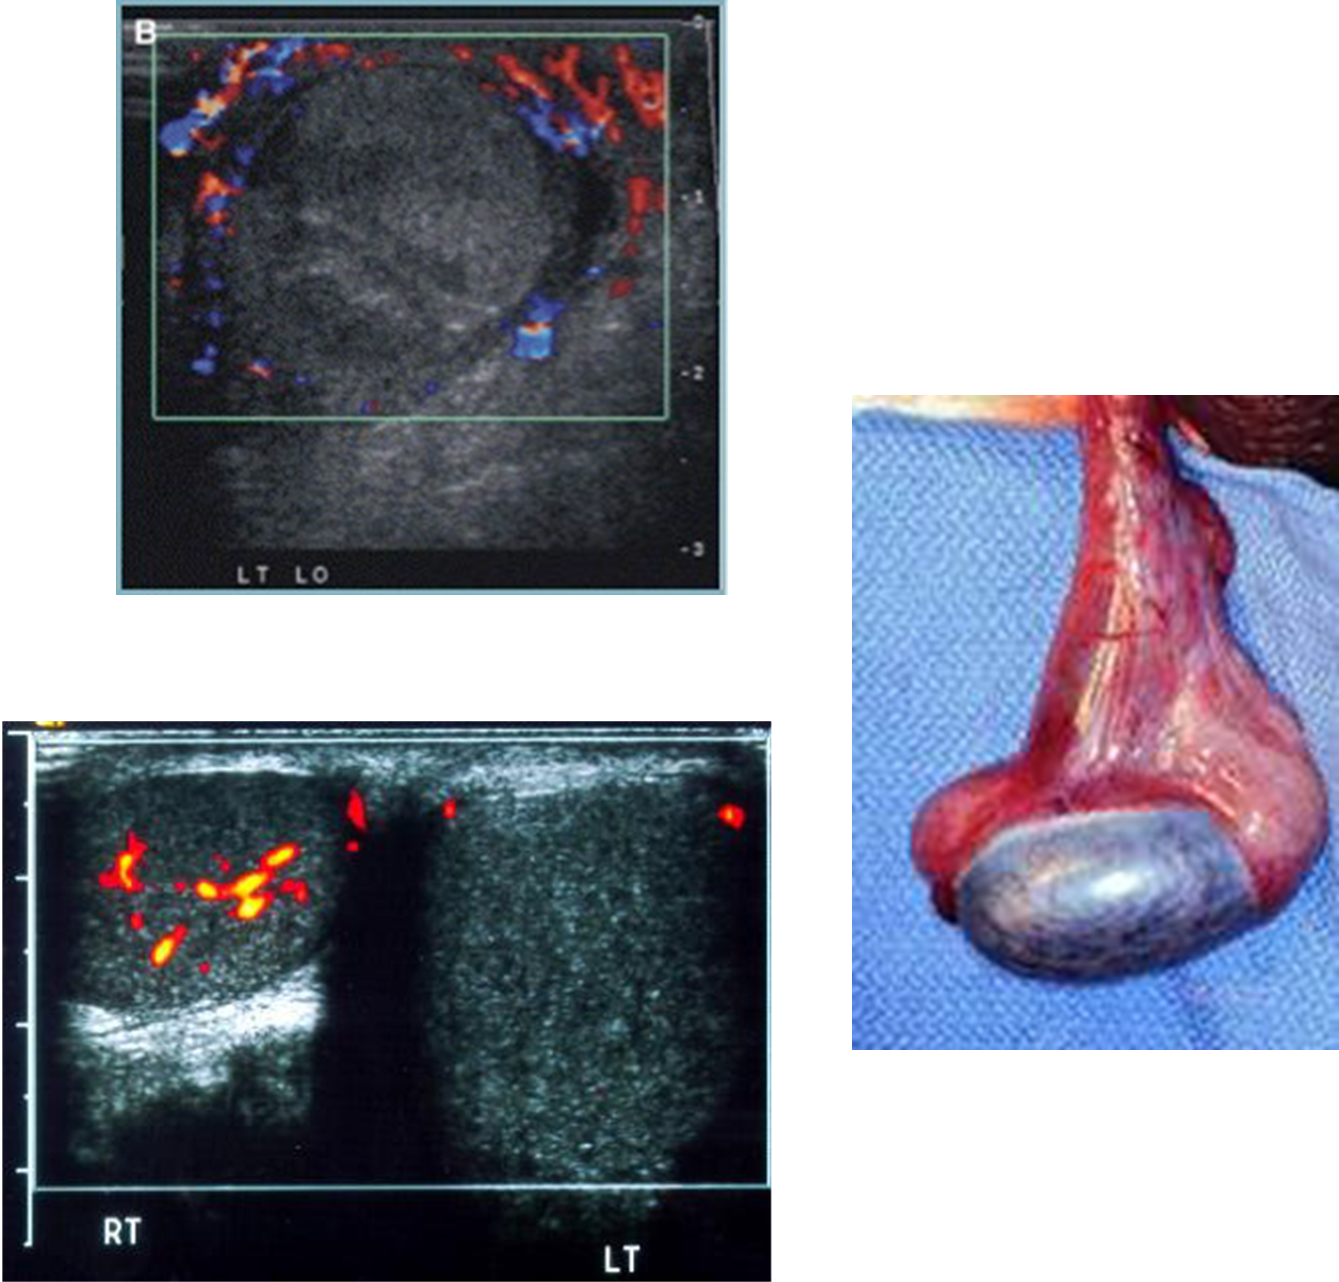

What is Testicular Torsion

Testicular Torsion is twisting of the spermatic cord leading to ischemic damage of the testis

1) often occurring due to insufficient fixation of the testicle by the gubernaculum leading to it rotating “bell clapper deformity”

→ the testicle will lay horizontally instead of vertically and will have an absent Cremaster reflex

2) On examination will often see absent blood supply to the testis with abdominal pain and GI symptoms but have no fever or urinary complaints

→ it is considered a surgical emergency